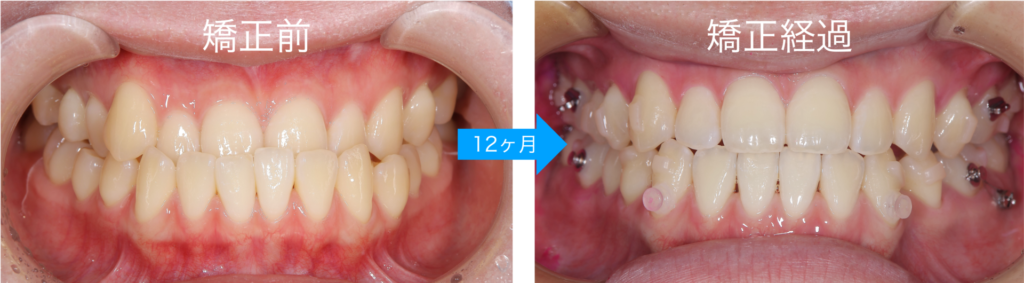

マウスピース矯正による治療経過になります

反対咬合は改善され、正常な咬み合わせに改善することができました

今回、患者様は非常にしっかりとマウスピースを着用していただけたため、12か月という短期間でここまで改善することができました